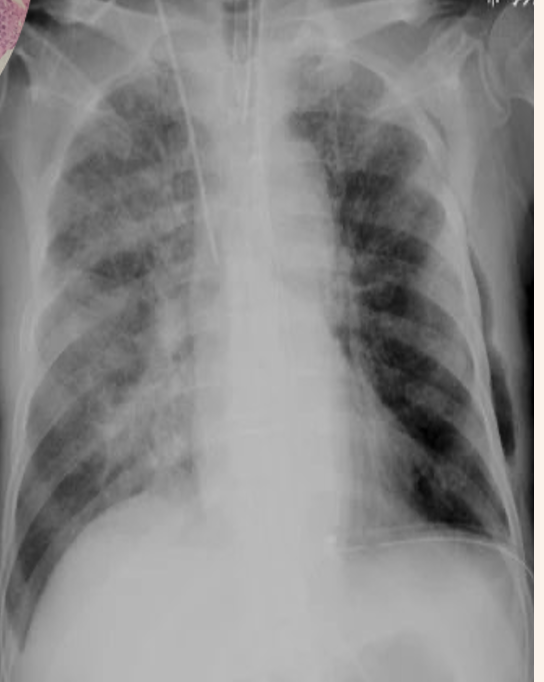

3 - wheezing, chronic bronchitis with diffuse pulmonaryinfiltrate

• wheezing, chronic bronchitis with diffuse pulmonaryinfiltrate